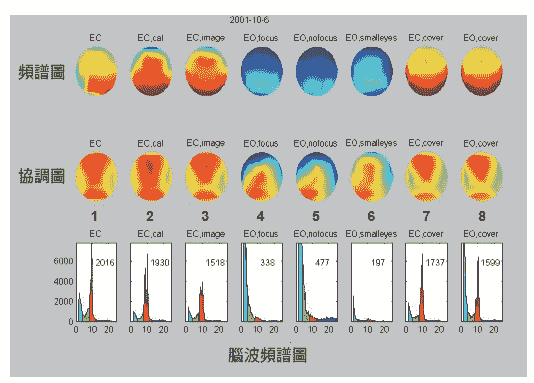

后来,我们也去新光医院测量手指识字时脑波的变化(如下页图2-12所示),量出的结果如一○一页图2-13所示,第一列及第二列为不同实验状况下脑波在全大脑的分布图。

第三列是大脑枕部(视觉处理部位)的脑波经傅立叶转换后的频谱图。横轴是频率,纵轴是强度。一般人的频率在十四到三十赫兹的是β波,八到十三赫兹是α波,四到七赫兹是θ波,四赫兹以下是δ波。

从第三列最左边第一张图来看,是眼睛闭上(EC,eye closed)的状况,其中红色的α波非常强,与一般人相同。第二张图是眼睛闭上在算数(EC,cal),例如计算二十七乘以三十五时,α波受到打扰稍微下降一些。第三张图是眼睛闭上在想风景(EC,image),例如想日月潭风景,红色α波受到打扰再稍微下降一些。

第四及第五张图是眼睛打开注意看外面景象(EO,focus)或随意看看(EO,nofocus),红色α波振幅受到严重干扰几乎消失。第六张图是眼睛打开一点点勉强看到外面的字或景象(EO,smalleyes),α波也受到严重干扰消失。第七及第八张图,只要戴上眼罩,则不管是闭眼或张眼都看不见外面景象,α波变得很强。

图2-13 手指识字时,在不同状况下的脑波分布和频谱图

|  |

|

| 从最下列第7、第8张图中可看出,当高桥用手指识字看到纸上的文字或图案时,眼睛并没有打开,看不到外面景象,因此α波会变得很强。 |

这些现象告诉我们,α波是一个严格的生理指标,可以让我们辨认受试者有没有看到外面的景象。我们想证明的是当高桥用手指识字看到纸上的文字或图案时,眼睛并没有打开,因此α波会变得很强。

左图2-14就是实验的结果,为手指识字时大脑枕部O1、O2及顶部T5、T6脑波频谱图,每一条线为十秒钟的数据,红色尖锋为α波振幅,黄色区间为酝酿期,双手有电压出现,紫色为开天眼区间。很明显的是,开天眼时,她脑中的α波振幅仍然很大没有变小,表示眼睛是闭着没有看到外界的文字或图案,但是天眼却能看到正确的图案。